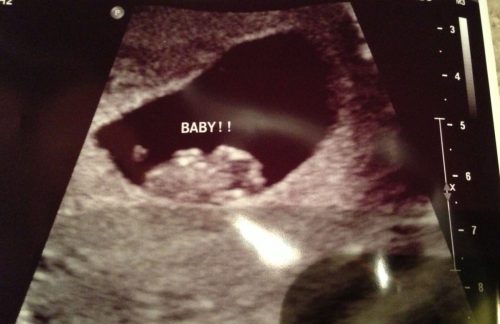

Das Ultraschallbild

Sieh dir die Bilder deines ersten Ultraschalls genauer an und beachte folgende Hinweise:

- Für den Fall, dass es sich um einen vaginalen Ultraschall handelt: Wenn sich der Fötus auf der linken Seite festgesetzt hat, ist es ein Mädchen. Wenn der Fötus rechts liegt, ist es ein Junge.

- Falls es ein abdominaler Ultraschall ist: In diesem Falle sollte man das Bild genau spiegelverkehrt analysieren. Wenn du also sehen kannst, dass sich die Plazenta auf der rechten Seite ist (was beutet, dass sie sich eigentlich auf der linken Seite befindet) dann erwartest du ein Mädchen. Falls du die Plazenta auf der linken Seite finden kannst (was bedeutet, sie ist auf der rechten Seite), bekommst du bald einen kleinen Jungen.

Keine Sorge, falls du Probleme damit hast, das Ultraschallbild zu interpretieren oder die Plazenta zu finden – frage einfach deinen Arzt danach!